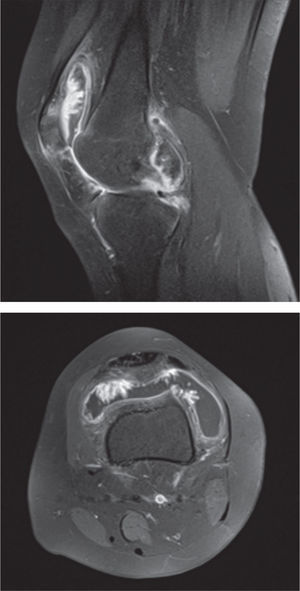

Fue solicitada la resonancia magnética nuclear (RMN) que evidenció moderado derrame articular con hipertrofia sinovial y una masa de partes blandas intraarticular, con hipointensidad en las secuencias T1 corte transversal y en la secuencia T2 corte sagital (fig. 2)

Dadas las dificultades para obtener un diagnóstico clínico y radiológico, los examenes complementarios pueden tener utilidad diagnóstica, sin embargo, la resonancia magnética es clave para la detección de este tipo de patología. En nuestra paciente la RMN en la secuencia T1 corte transversal y en la secuencia T2 corte sagital constituyeron un buen método auxiliar, dando la posibilidad de evaluar el tamaño, posición y características de la masa tumoral, revelando un derrame articular moderado con hipertrofia sinovial. Datos que coinciden con lo reportado en la literatura, donde los depósitos de hemosiderina se muestran con hipointensidad en las secuencias de la RMN19.